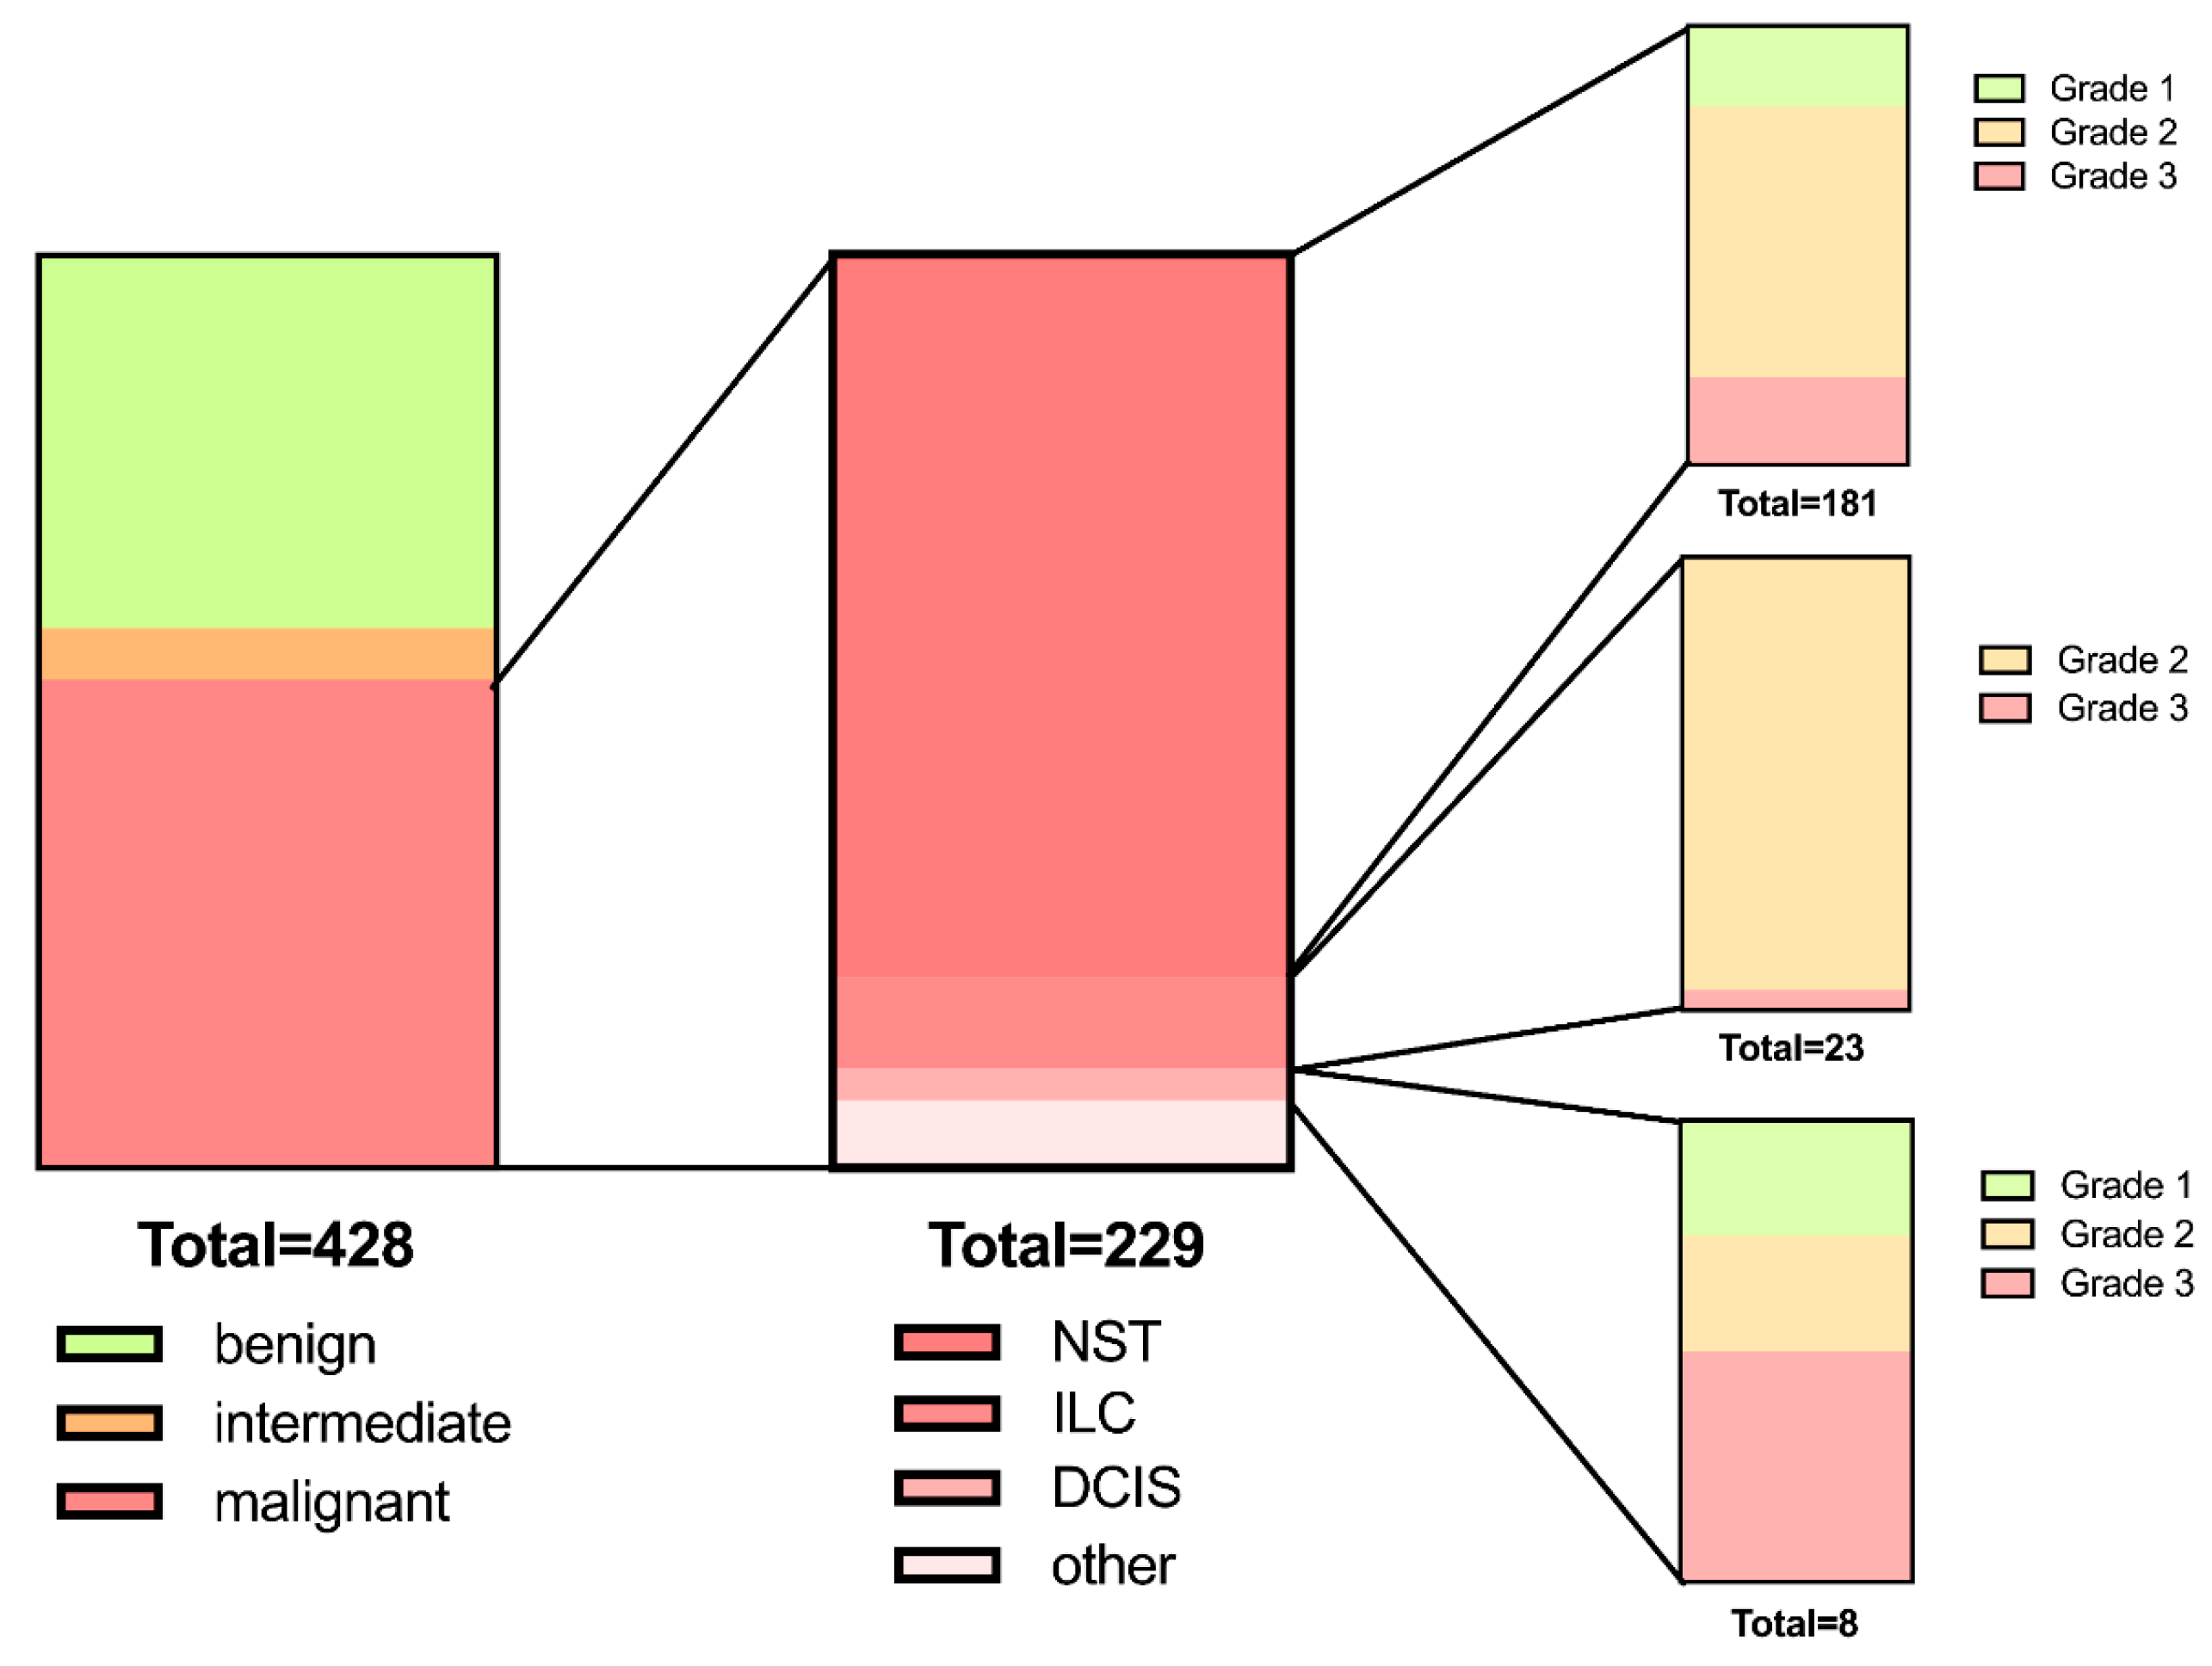

3.1. Patient Demographics and Lesion Characteristics

| n | 428 | 175 | 24 | 229 | n/a |

| Age [years] | 56.0 ± 16.5 | 48.3 ± 14.8 | 54.2 ± 16.3 | 62.2 ± 15.3 | 0.284/<0.0001/0.066 # |

| Maximum diameter (mm) | 15.4 ± 9.0 | 14.9 ± 9.4 | 16.4 ± 10.8 | 15.7 ± 8.6 | >0.999/0.316/>0.999 # |

| Grade 1/2/3 (%/n) | - | - | - | G1: 23.8% (43) G2: 78.5% (142) G3: 24.3% (44) | n/a |

| Quadrant UI/ LI/ LO/ UO/ C (%/n) | 16.6% (71)/ 8.9% (38)/ 19.2% (82)/ 48.8% (209)/ 6.5% (28) | 17.1% (30)/ 9.7% (17)/ 21.7% (38)/ 42.3% (74)/ 9.1% (16) | 12.5% (3)/ 12.5% (3)/ 16.7% (4)/ 41.7% (10)/ 16.7% (4) | 16.6% (38)/ 7.9% (18)/ 17.5% (40)/ 54.6% (125)/ 3.5% (8) | 0.076 § |

| Lymph node metastasis (%/n) | - | - | - | 18.3% (42) | n/a |